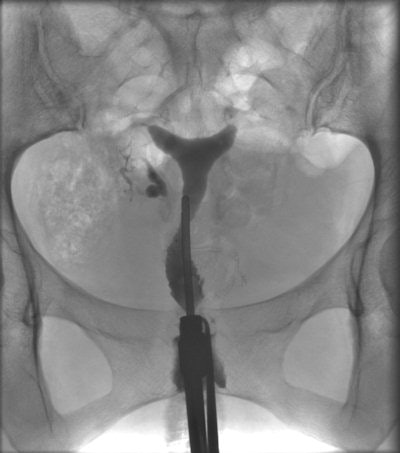

HSG of a 38-year-old patient with irregular nodular configuration of the right tube (salpingitis isthmica nodosa). The left tube is proximally occluded. Because the patient had decided that she did not want more children, there was no further workup. The HSG was performed to assess the need for anticonception.The researchers acknowledge the limitations in their study. No follow-up information was available for 23% of the patients with a pathological condition at HSG. It is unknown how many of these patients became pregnant.